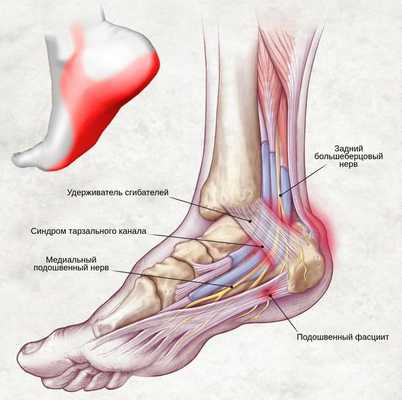

Синдром тарзального канала

Синдром тарзального канала (СТК), либо, как еще называют данный недуг - туннельный синдром предплюсны, представляет собой заболевание, сопровождаемое дискомфортными и болевыми ощущениями, спровоцированными чрезмерным сдавливанием и натяжением расположенного в канале предплюсны большеберцового нерва.

Проходящий по поверхностям таранной и пяточной костей (в задней части лодыжки), канал предплюсны ограничивается удерживателем сухожилий-сгибателей. Постоянное раздражение находящегося в канале нерва вызывает стопное онемение и, соответственно, боль в данной области.

С точки зрения анатомии, канал предплюсны представляет собой пространство, где размещены сухожилия сгибателей пальцев (в том числе и первого), а также большеберцовые нерв и артерия. В свою очередь, большеберцовый нерв подразделяется на латеральный, пяточный и медиальный нервы.

Рис 1. Анатомические особенности канала предплюсны.

Удерживатель сгибателей представляет собой связку, которая, в норме, ограничивает канал предплюсны, а также удерживает находящиеся в нем анатомические элементы. Однако, при этом, именно связка может спровоцировать различного рода нарушения анатомической структуры голеностопа и стопы путем патологического сжимания содержимого канала.